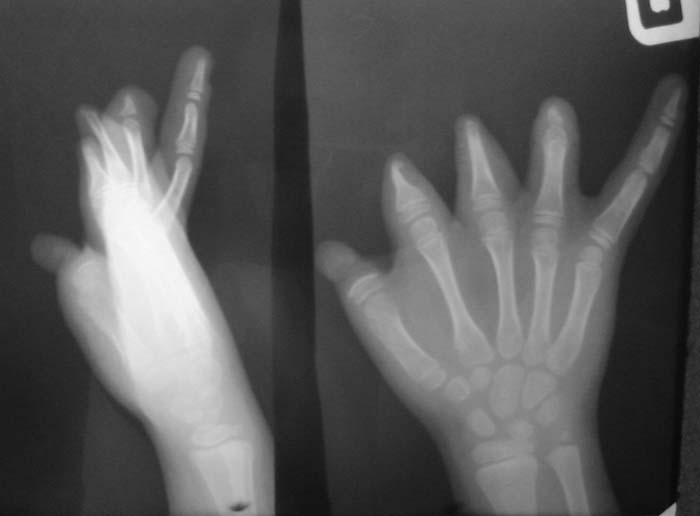

Уважаемые коллеги!Девочка, 6 лет. Врожденная аномалия развития кистей и стоп.Вопрос: лечение?В приложении - рентгенограммы и клинические фотографииЗаранее благодарен!С уважением,А.В.Владзимирский

Без рентгенограмм костей левой стопы, голени и голеностопного сустава определение тактики лечения левой нижней конечности невозможно. А с кистями рекомендую направить в специализированное отделение института им.Турнера (для удлинения фаланг пальцев с использованием микрохирургической техники)e-mail института им.Турнера: turner@admiral.ru

Уважаемый коллега!

Мы благодарны Вам за выраженное доверие к сотрудничеству.

Продемонстрированный вами случай весьма интересен.

Исходя из возможностей современной реконструктивно-пластической хирургии

с целью восстановления функции захвата правой кисти целесообразна пересадка

пальца стопы в позицию первого луча. В этом случае пересадка второго пальца

левой стопы невозможна из-за аплазии донорской зоны. Поэтому здесь допустимо

произвести реконструкцию области дефекта пересадкой второго пальца левой

стопы. Необходимо учитывать и этиологию дефекта - врождённая аплазия, что

является одним из противопоказаний к реконструкции - отсутствие корковой

интеграции. Учитывая возраст больного это противопоказание условное. В таких

случаях, по литературным данным, допустимо проведение реконструкции до

десятилетнего возраста - возможность перестройки цереброкортикальной

интеграции при условии проведения соответствующего реабилитационного

лечения.

Пациенту необходимо воосстановить опорную функцию правой нижней

конечности.

Безусловно девочке необходимо создать 1-й палец правой кисти - создать противопоставление остальным пальцем и таким образом получить функцию захвата. Варианты операций:

1. Пересадка 2-го пальца стопы (предварительно сделав доплерографию стопы и кисти)

2. Транспозиция культи 3 или 4-го пальца в положение 1-го.

3. Несвободная пересадка комплекса тканей на a. radialis в который входит участок лучевой кости (реверсионный лучевой лоскут с костным фрагментом для восстановления 1-го пальца.

4. Возможна свободная костная пластика (например, фрагмент в/3 большеберцовой кости кости с одновременной кожной пластикой по Блохину-Конверсу.

В каком состоянии сейчас находится сухожильно-мышечный аппарат правой кисти?

Обратите внимание на культю 2-го пальца - может необходимо резецировать острый костный конус с пластикой кожи над ней?